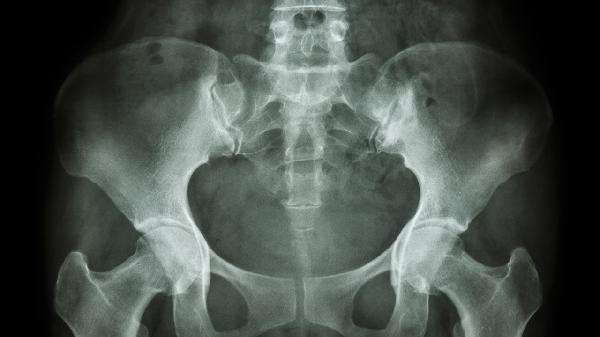

均小骨盆可分为扁平型骨盆、漏斗型骨盆、横径狭窄型骨盆、畸形骨盆和均小型骨盆五种类型。均小骨盆是指骨盆各径线均小于正常值,可能影响分娩过程,需要根据具体类型采取不同处理措施。

扁平型骨盆主要表现为骨盆入口前后径明显缩短,横径相对正常。这种类型骨盆可能导致胎头入盆困难,增加难产概率。产前检查可通过骨盆外测量和内测量发现异常,必要时需进行影像学检查确认。处理上可尝试改变体位促进胎头入盆,若效果不佳可能需要考虑剖宫产。

漏斗型骨盆特点是骨盆入口各径线正常,但中骨盆和出口平面逐渐狭窄。这种类型骨盆容易导致分娩过程中胎头下降受阻,出现第二产程延长。临床表现为胎头下降停滞,产程进展缓慢。处理措施包括密切监测产程进展,必要时使用产钳助产或转为剖宫产。

横径狭窄型骨盆表现为骨盆各平面横径均小于正常值,前后径相对正常。这种类型骨盆可能影响胎头在骨盆内的旋转机制,增加持续性枕横位的发生概率。产程中可能出现胎头旋转异常,导致产程延长。处理上可尝试手法旋转胎头,若失败则需考虑手术助产或剖宫产。

畸形骨盆多由外伤、骨病或发育异常引起,表现为骨盆形态不对称或结构异常。这种类型骨盆可能严重影响分娩机制,增加母婴并发症风险。临床表现包括胎位异常、产道梗阻等。处理上通常需要提前评估,多数情况下建议择期剖宫产。

均小型骨盆是指骨盆各径线均按比例缩小,但形态基本正常。这种类型骨盆可能导致相对头盆不称,增加难产风险。临床表现主要为产程进展缓慢,胎头下降困难。处理上可尝试阴道试产,但需做好随时转为剖宫产的准备。